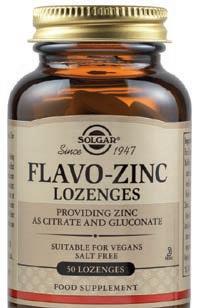

+ Vitamin C + Zinc

+ Vitamin C + Zinc